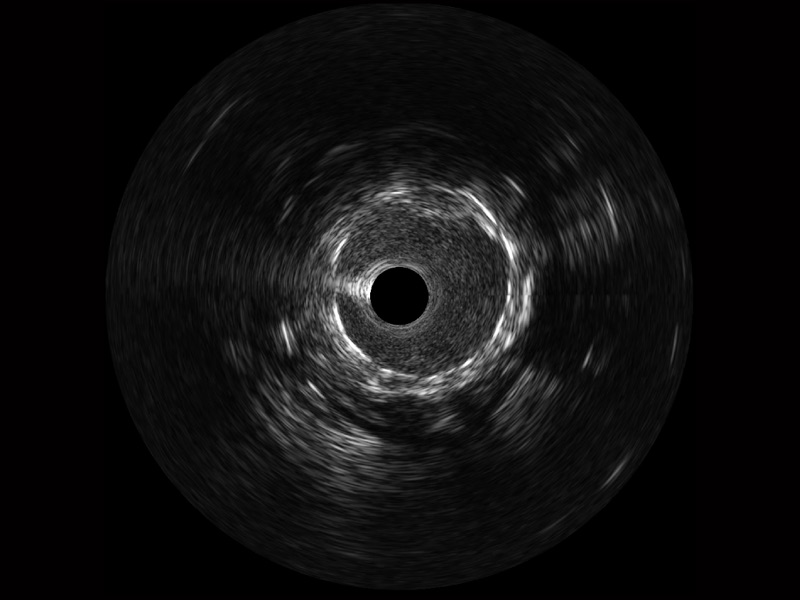

• db真人体育官网宽频IVUS图像

• 传统IVUS图像

对比传统IVUS导管成像,db真人体育官网宽频IVUS图像的近场支架梁显影更细腻,远场中膜外血管仍清晰可辨,兼顾远中近,兼顾分辨力与穿透深度

临床图

远场分支血管及导丝

支架内血栓

组织脱垂